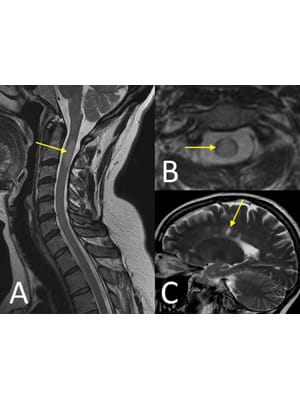

With respect to MRI technique, high quality T2 sequences are essential to ensure good sensitivity for cord lesions and to allow accurate delineation of the extent of lesions. The sagittal T2 sequence shows the longitudinal extent of lesions, while the axial T2 sequence shows the location of lesions within the cord in cross-section. Both of these features are important discriminators. In addition, post-contrast T1 sequences are useful in demonstrating the enhancement pattern of cord lesions, which may also help to distinguish between different pathologies.